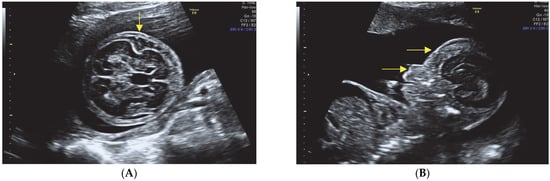

- Hypomineralization of the skull bones.

- Enlarged head and small face.

- Narrow thorax with evidence of pulmonary hypoplasia.

- Multiple rib fractures.